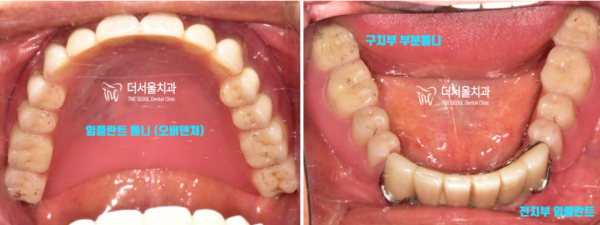

실제 오버덴쳐를 부착한 형태입니다.

기존의 틀니보다 아주 보기 좋고 불편하지 않은

임플란트 틀니입니다.

환자분께서도 아주 만족하셨던 오버덴쳐 치료였습니다.

The actual overdenture is attached.

It looks better and is less uncomfortable than conventional dentures

It's an implant denture.

It was an overdenture treatment that you were very satisfied with.